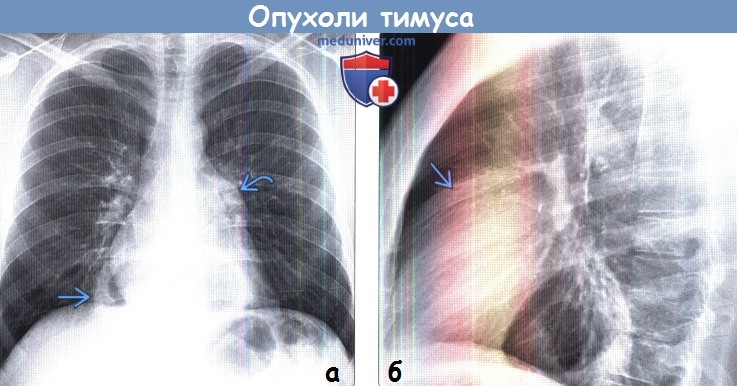

Тимомегалия: что это такое и как проявляется